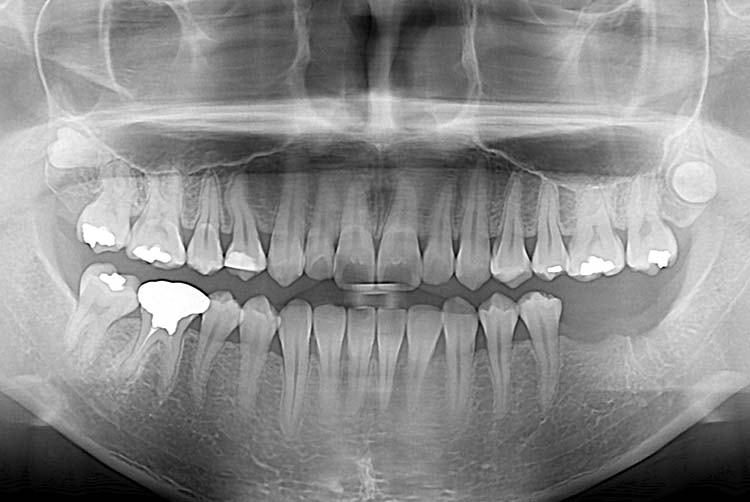

[임플란트] 임플란트

치료전 : 2015-04-21

치료후 : 2019-10-14

세종치과는 많은 환자와 다양한 케이스를 바탕으로 항상 편안한 임플란트 수술을 제공하고자 노력하고,

오래동안 튼튼히 쓸 수 있는 임플란트 수술을 가장 큰 목표로 삼고 있습니다.